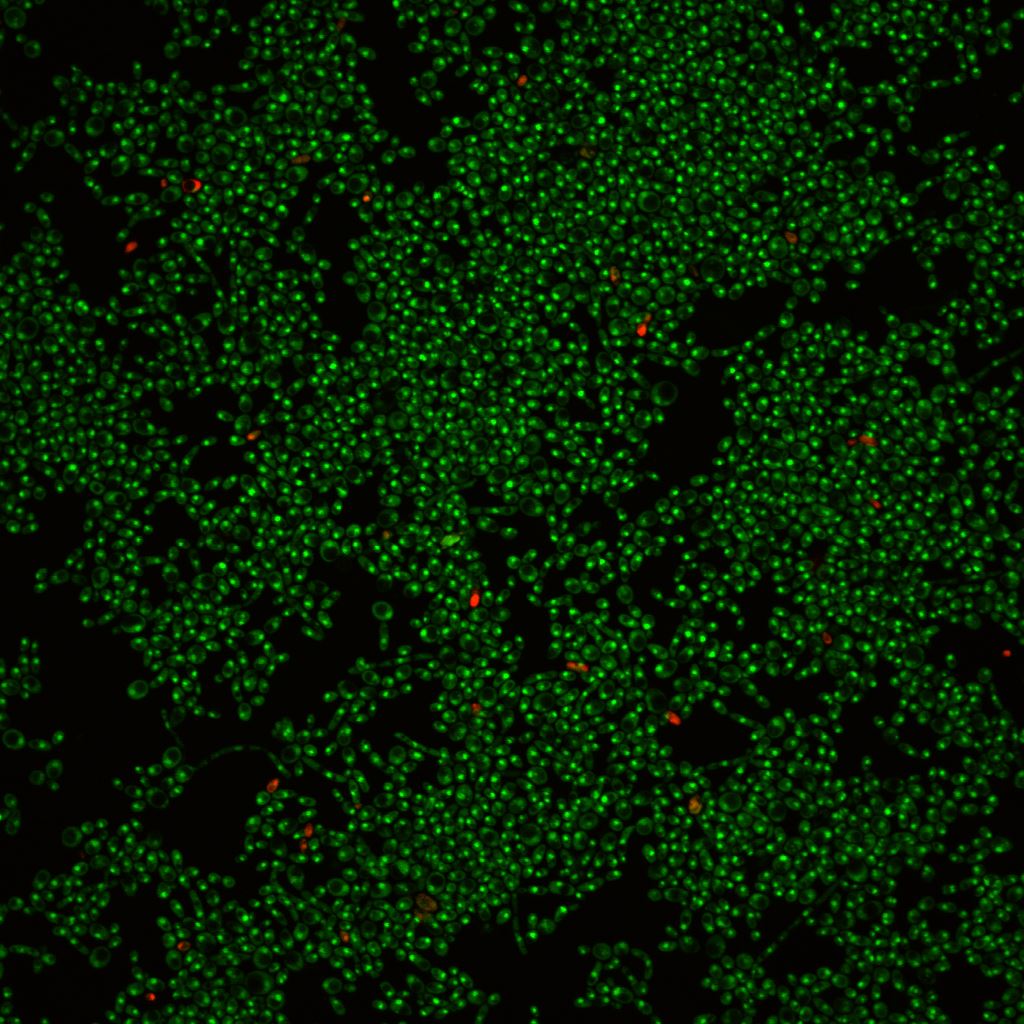

研究團隊發現紅紫素能有效抑制白色念珠菌在塑料表面生長及生成菌膜(也稱生物膜);它亦能破壞已生成熟之生物膜。相關研究結果已在國際期刋PLoS ONE發表。

研究報告指出,紅紫素大大減低白色念珠菌在塑料表面生成生物膜之能力,其效力呈濃度依賴關係。加入3µg/mL之的紅紫素可抑制生物膜之形成約44%;提高紅紫素之濃度至10µg/mL更可抑制生物膜之形成達約64%。然而,同等份量之紅紫素對抑制已形成之白色念珠菌生物膜之效用較差,分別為約6%及約37%。研究團隊表示已形成之生物膜結構非常緊密,增加其抗藥性。

研究團隊利用電子顯微鏡掃描白色念珠菌生物膜,發現加入3µg/mL之紅紫素能有效抑制生物膜之形成,並顯示構成生物膜之細胞主要呈現酵母菌狀態,由此證明該濃度之紅紫素足以抑制白色念珠菌轉化為菌絲狀態--另一種致病因子。研究團隊進一步確認紅紫素抑制白色念珠菌轉化為菌絲之效力在液體或固體培養基中並無差異。